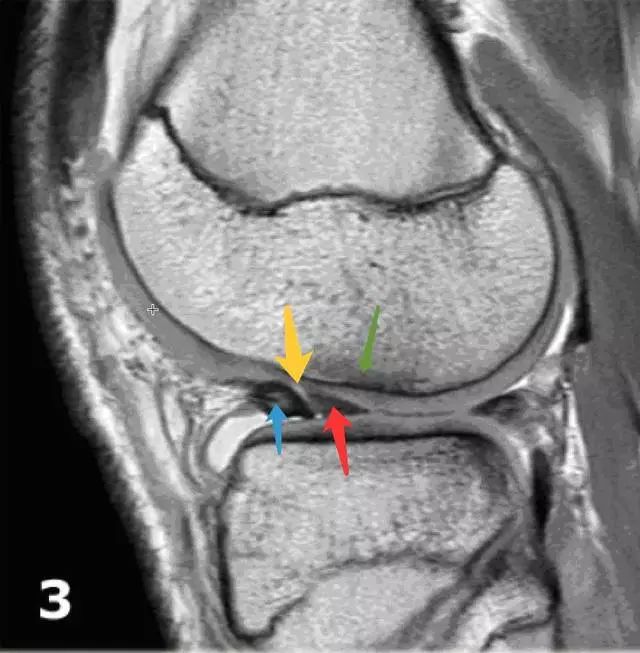

图 12 半月板翻转

半月板翻转是一种特殊的半月板桶柄状撕裂。左图:可看到半月板前角(红色箭头)较大且边缘不规则,后角(蓝色箭头)较小。右图:半月板前角线性增强处(黄色箭头)易误诊为前角纵行撕裂,实际为前后角重叠的交界,其前方(蓝色箭头)为半月板前角,后方(红色箭头)是后角撕裂后翻转过来的部分。同时可看到局部的骨髓水肿和软骨压迫(绿色箭头)。